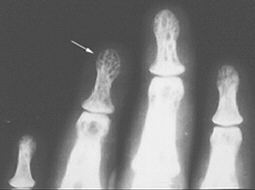

Refer to the picture above for question 4.

4. Recognized causes for the above condition include:

Refer to the picture above for question 5.

5. Causes of the above appearance include: